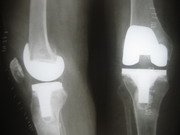

Knee Joints Case B

Knee Joint Replacement Knee Joint Replacement Knee Joint Replacement